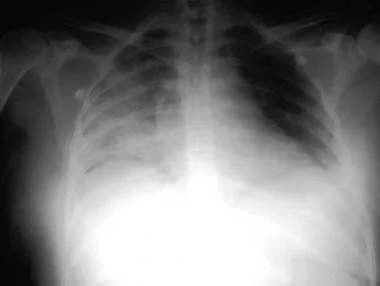

厌氧性细菌性肺炎患者的胸部影像学通常显示浸润,有或无空洞。透明的浸润物提示为坏死性肺炎。浸润周围的气液平面表明存在肺脓肿。肋膈角变钝是肺炎旁胸膜积液的征象。

全血分析5分类是什么详解:吸入性肺炎表现、诊断与检测!│临床必备_https://www.jmylbn.com_新闻资讯_第2张

图2 患者男,84岁,吸入性肺炎。后前位X线片显示左下叶不透明影